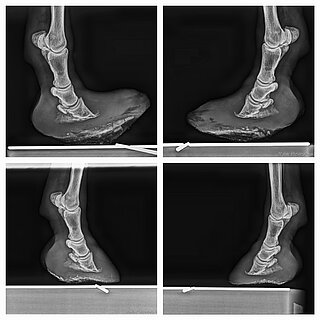

• | Röntgenuntersuchung | |

• | Evtl. Hufkorrektur anhand der Röntgenbefunde | |